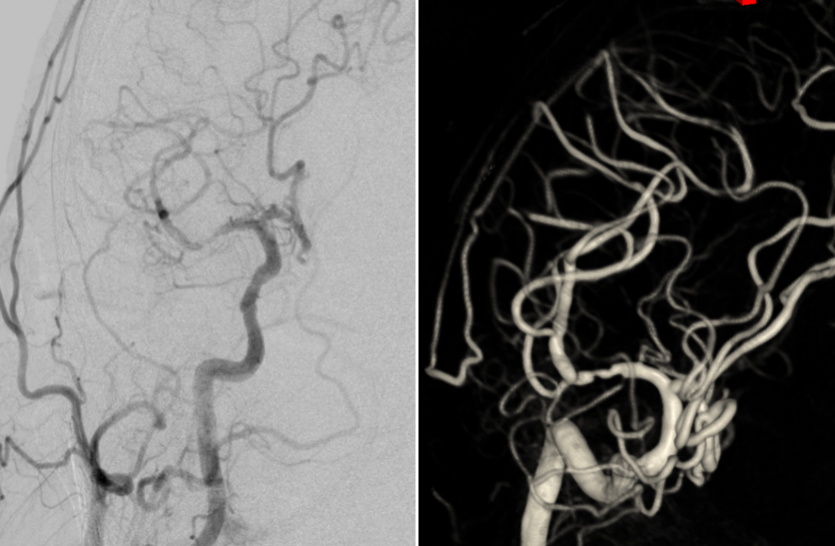

DSA:右侧大脑中动脉M1段管壁不规则溃疡斑块形成,局部重度狭窄

术后DSA:右侧大脑中动脉未见明显残余狭窄,远端分支未见残端